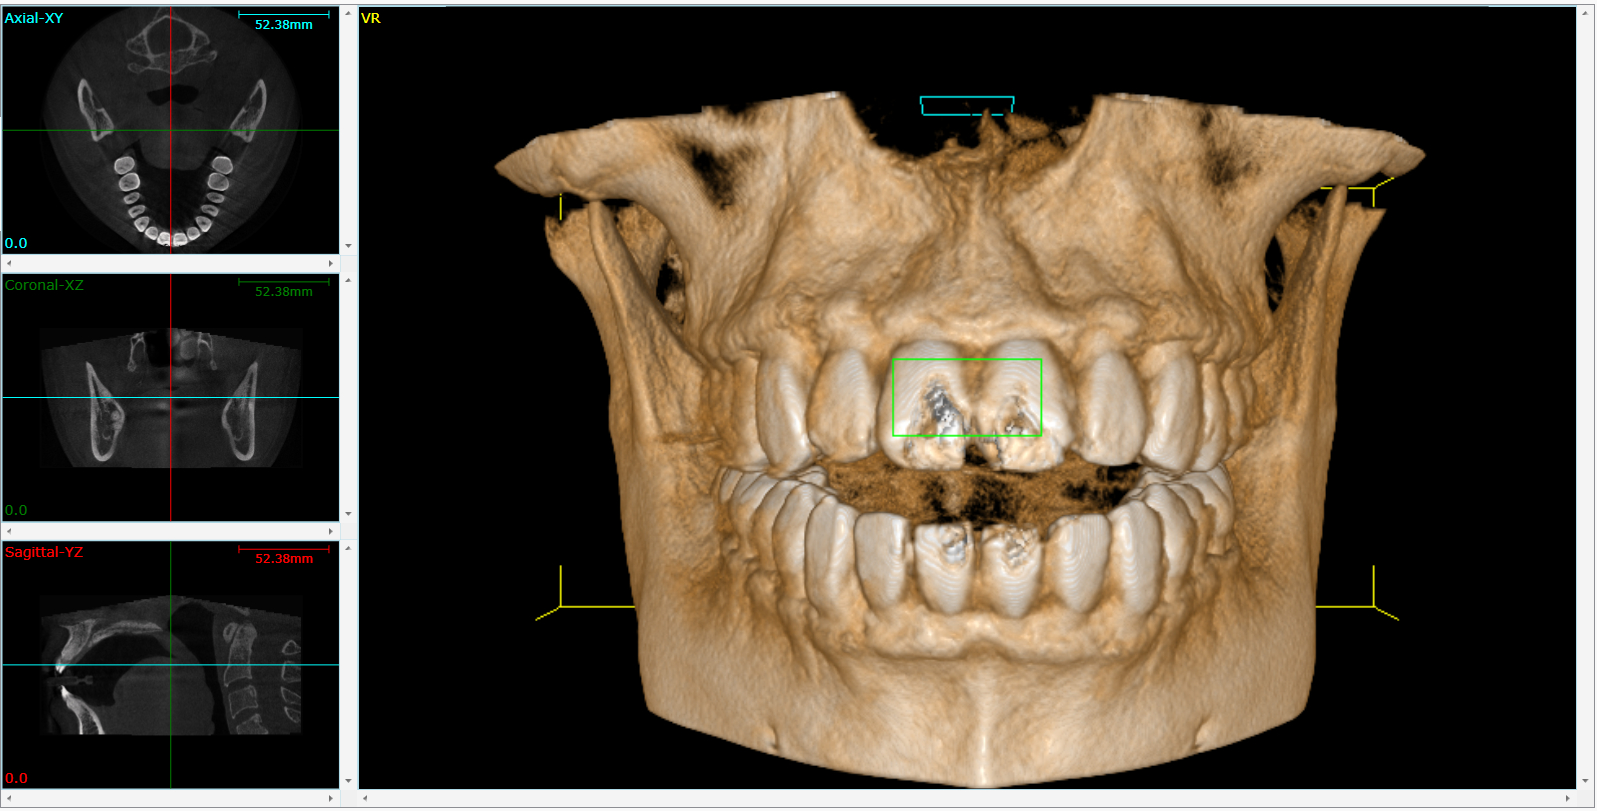

Questa immagine di seguito, mostra immagini 3D acquisite con un apparecchio TC Cone Beam.